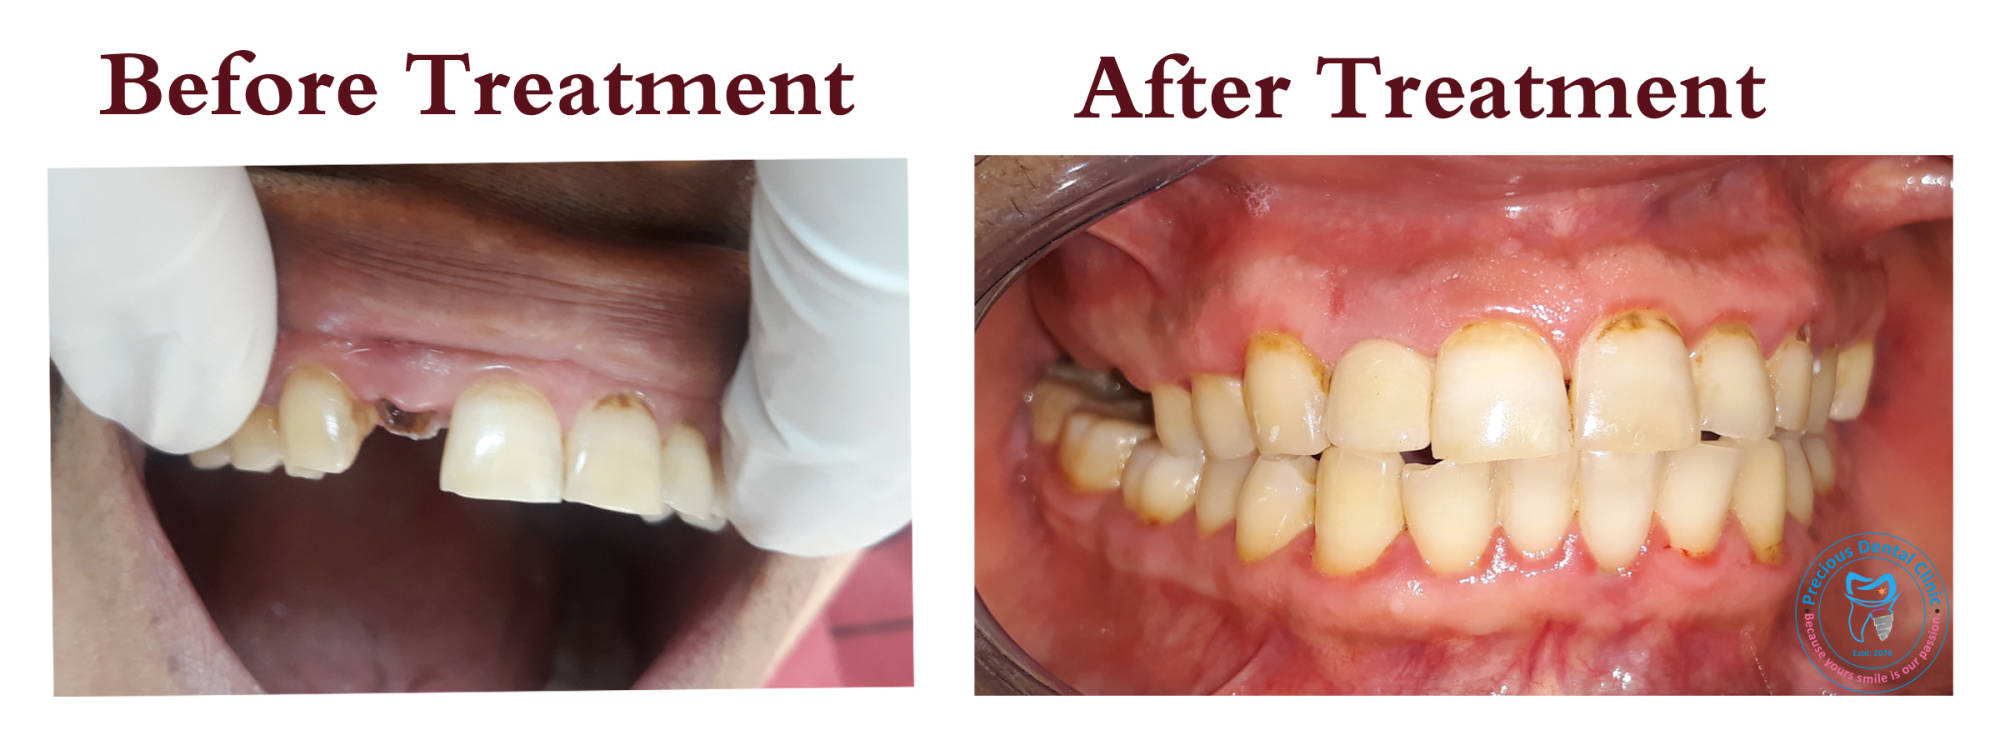

Post and Core

Post and Core Ulcer